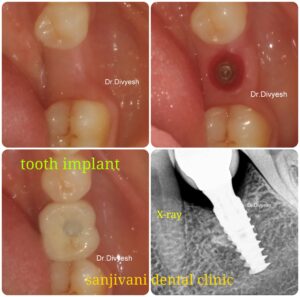

અમારી હોસ્પિટલ માં કરેલ ડેન્ટલ ઇમ્પ્લાન્ટ ના ફોટો

બીજા તબક્કામાં ઇમ્પ્લાન્ટ મૂકવામાં આવે છે.

ત્રીજો તબક્કામાં ઇમ્પ્લાન્ટ કનેક્શન (abutment) મૂકી ફિક્સ દાંત લગાવવામાં આવે છે .